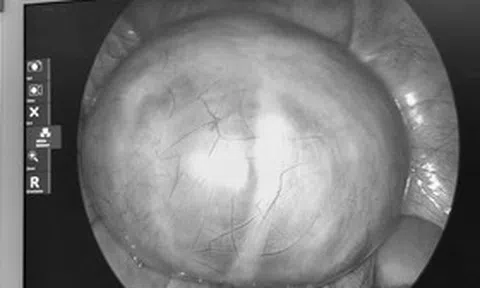

Người phụ nữ 42 tuổi đang khỏe mạnh bỗng ngất xỉu tử vong. Ảnh minh họa.